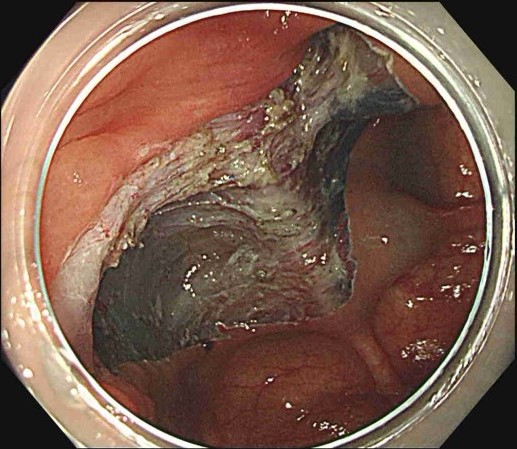

ESDの手順

Figures adapted from: Nagata M. Endoscopy 2024; 56: E699–E700.

Licensed under CC BY 4.0 (https://creativecommons.org/licenses/by/4.0/)

- 大きな病変でも一括切除が可能

- 正確な病理診断ができる

- 再発率が低い